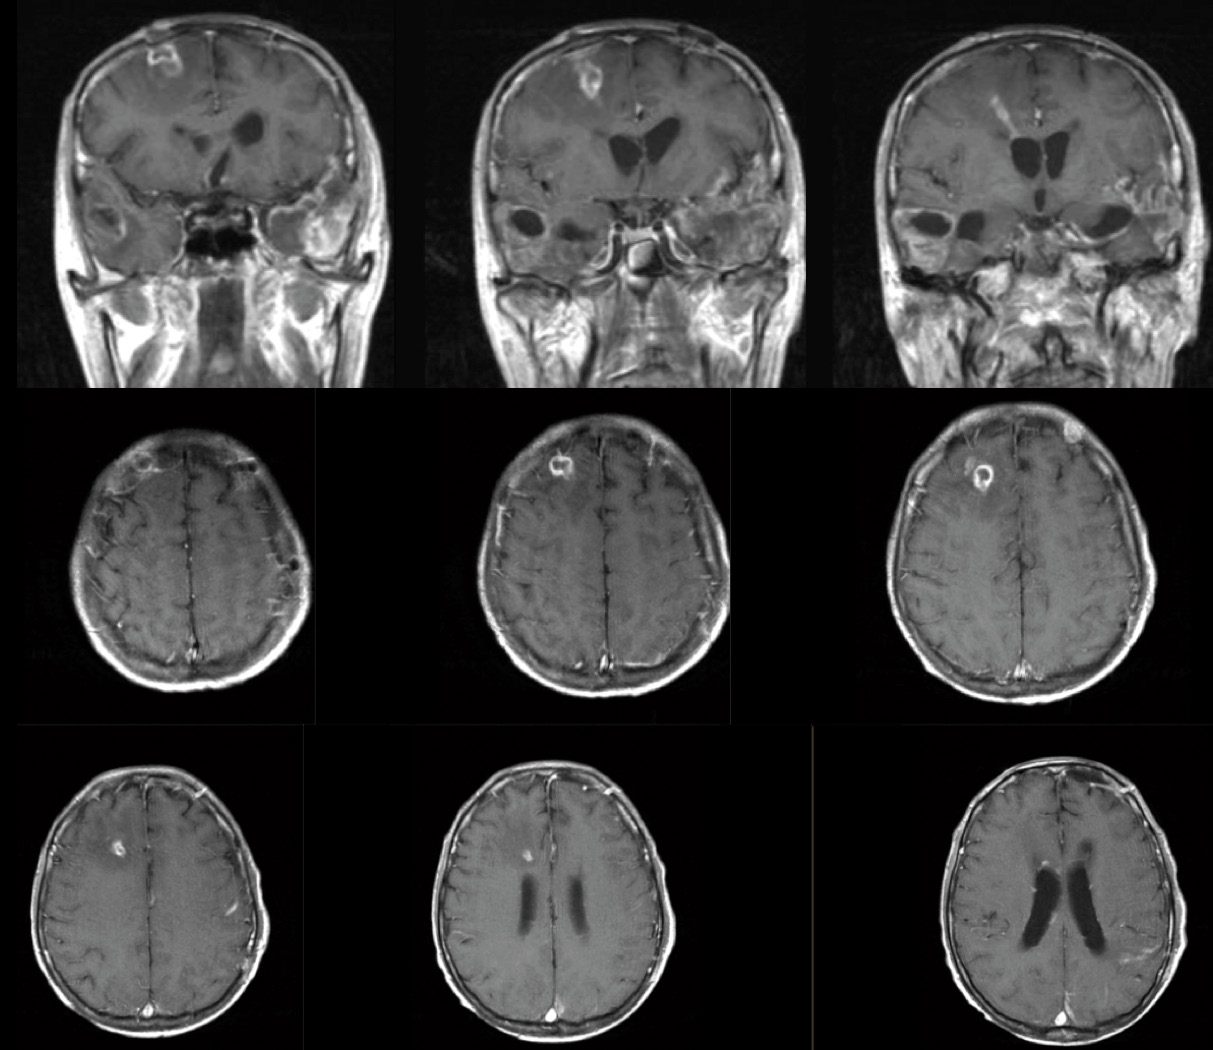

As he remained well with a clean ex-EVD exit site on repeat examination, the patient continued to be closely monitored but nothing further was done with regards to the culture report. However, one week later, he spiked a new fever with leukocytosis. A CT head showed inflammation along the tract of the former EVD (figure below), while CSF obtained via lumbar puncture showed an elevated CSF white cell count (307 cells per cubic millimetre of CSF), with elevated CSF protein and low CSF glucose. CSF galactomannan index was also high at >5.0.